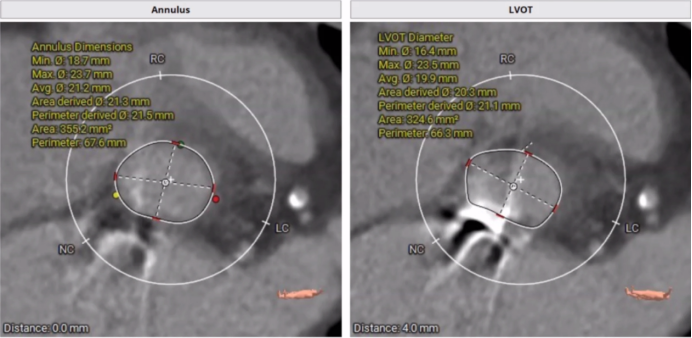

主动脉瓣膜CT影像

手术策略:全身麻醉、右股入路、无预扩张、23mm或26mm可回收输送系统。

针对该患者有轻度钙化、瓣环直径21mm,与会专家建议可以预扩,若不行预扩,则先要做好冠脉保护。此外,考虑到患者二尖瓣机械瓣置换术后,本次TAVR手术是否会出现瓣架展开问题,以及是否对机械瓣有影响也是重点关注的内容。对此,参照文献专家建议需注意:

1.术前应对二尖瓣进行详细评估,使用经食管超声心动图(TEE)和多层计算机断层扫描(MSCT)评估主动脉瓣、机械般之间距离;